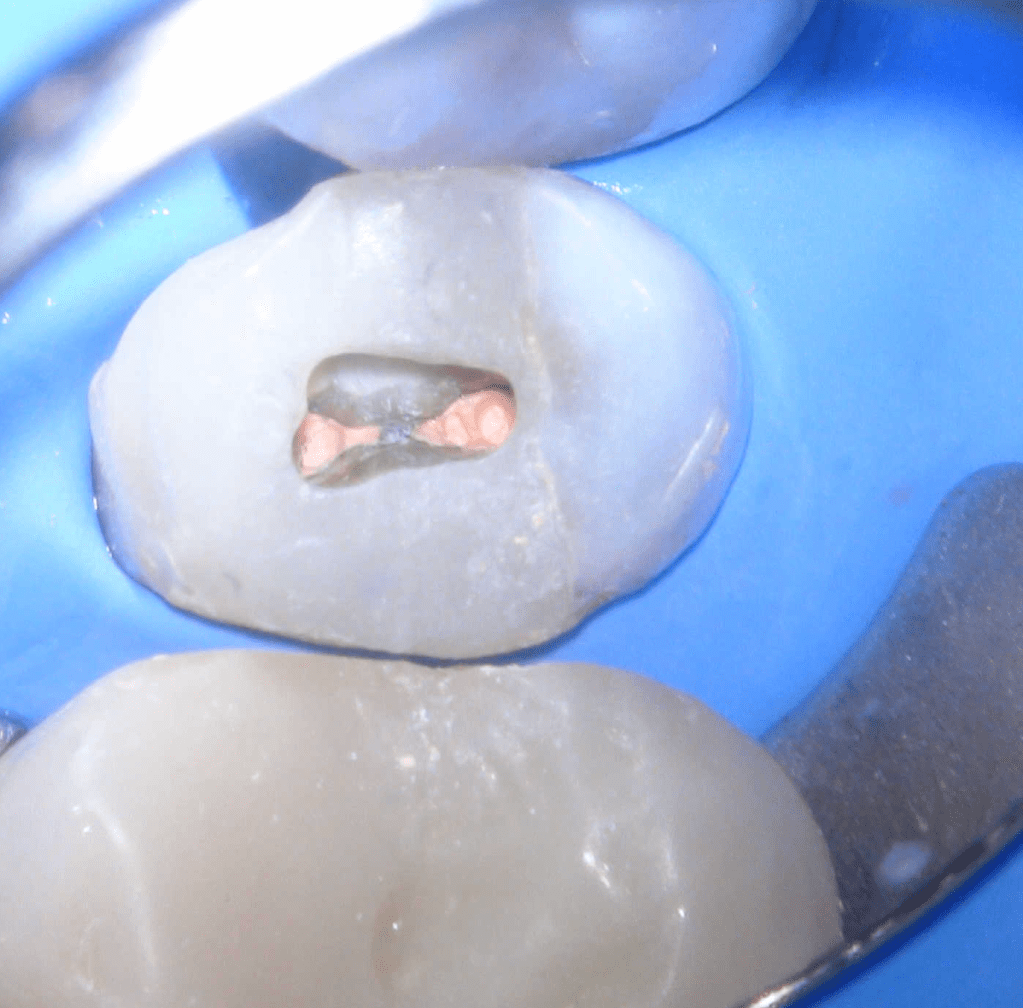

Pulpotomía biodentine + reco preendio